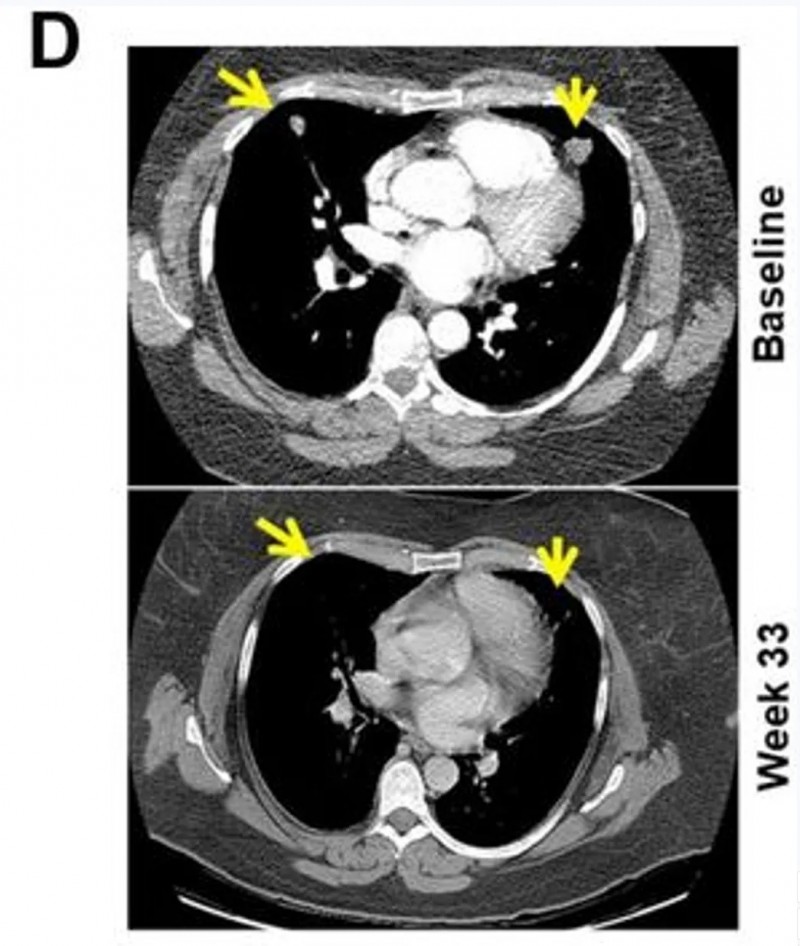

一项发表在《癌症免疫治疗杂志》上的前瞻性II期试验(NCT01876212)为联合治疗提供了证据。该研究针对15例PD-1抑制剂耐药的晚期黑色素瘤患者,使用“树突状细胞疫苗+达沙替尼”方案。

结果显示:从一开始就联合用药的B组,疗效远优于后期才联合的A组:客观缓解率达到66.7%,中位总生存期延长至15.45个月(对比3.47个月)。

值得一提的是,B组2例代表性患者经联合治疗后,内脏转移瘤明显缩小,并产生了协同免疫反应,最终达到客观部分缓解(PR)标准。

▲图源“JITC”,版权归原作者所有,如无意中侵犯了知识产权,请联系我们删除